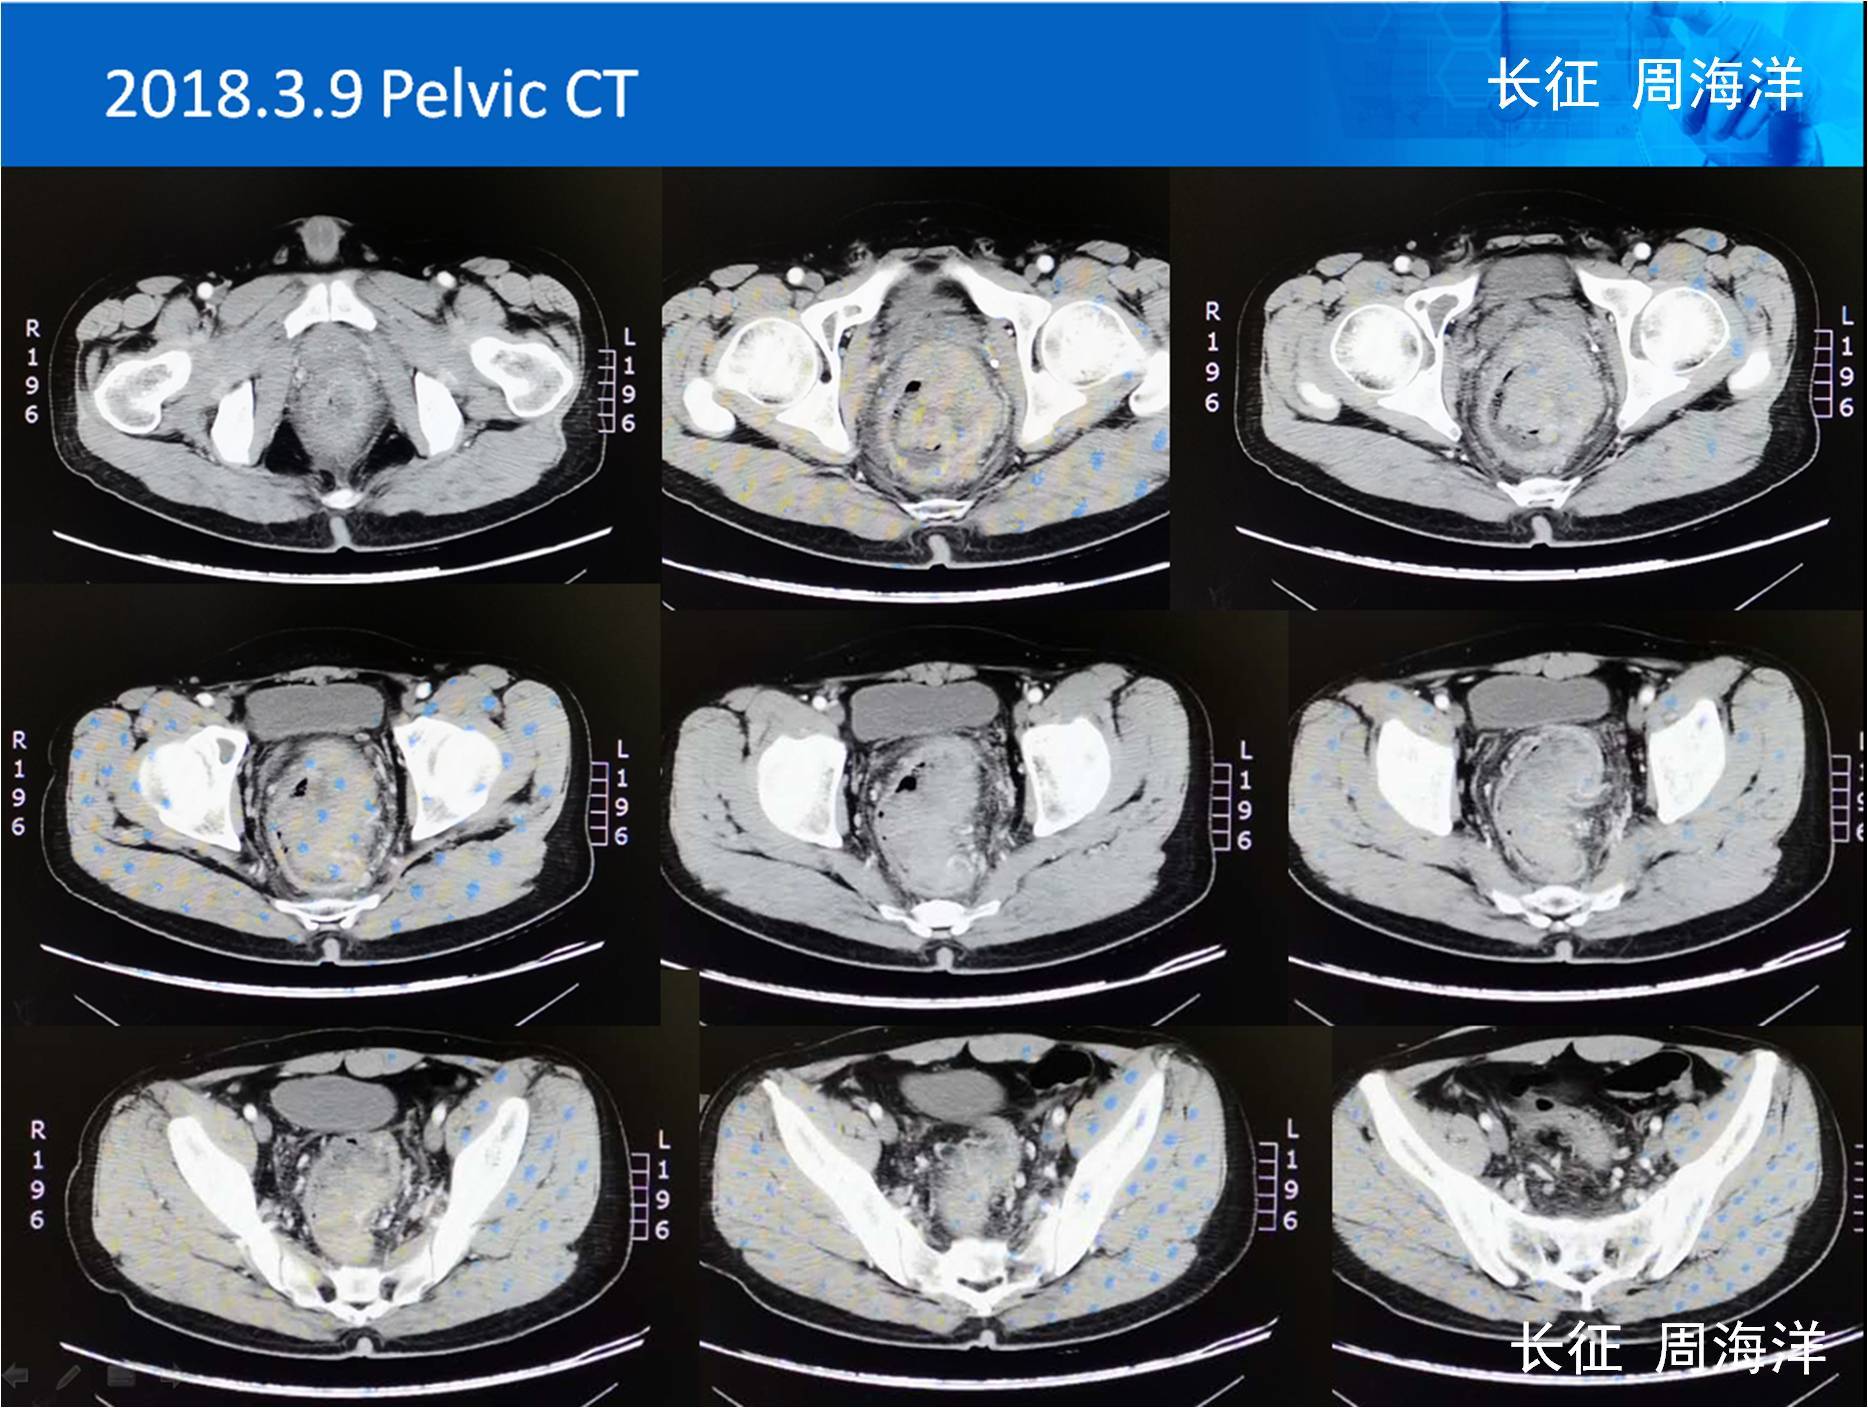

直肠癌一例

肿瘤病灶术前ct:箭头所指为左侧盆腔侧方淋巴结患者为局部晚期直肠癌

及局部放疗,治疗后盆腔ct如下,最终完成腹腔镜直肠癌根治术(保肛低位